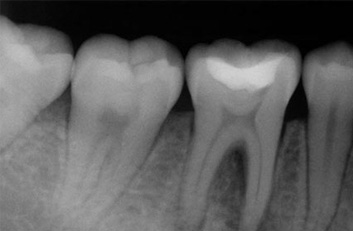

Root Canal, is a treatment that is made as the last resource before the extraction of any dental piece. When the cavity is so deep, this could touch the tissues searching the pulp, this happens when a cavity was not treated in time and pain appears when cold and hot food is tried. The pain could be unbearable and this is exactly what we pretend to avoid by performing an root canal treatment, to stop the unbearable pain or infection and the consequent loss of a dental piece.  An root canal treatment is not painful; it feels the same as a normal cure. The endodontic is unavoidable if you wish to preserve the dental piece. Without medical treatment, the tissue that surrounds the dental piece would be infected that’s why it can’t be filled in the normal way because if it happens, the piece would continue aching, the sensibility would be increasing and the infection would produce the loss of the piece.

During the root canal treatment, the nerve and the pulp are eliminated and the tooth gets cleaned inside, the root is filled with the correct materials and the next step is the reconstruction of the dental crown. All this treatment is performed by applying local anesthesia, the same anesthesia that is used in a common procedure.